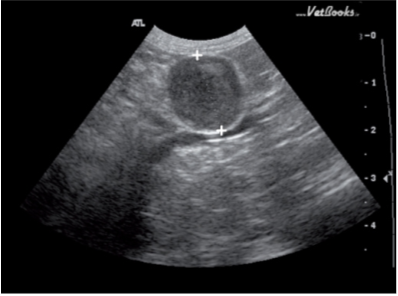

肾上腺肿瘤的超声表象包括肿块,钙化和异常回声(图4)。需要注意的是,增大的肾上腺或肾上腺肿块并不意味着它会分泌过多的醛固酮。这些肾上腺上的肿瘤但不引起临床症状的称为偶发瘤。功能性肿瘤会分泌如皮质醇,孕激素等激素,嗜铬细胞瘤也属于功能性肿瘤。

最近的一项研究将肾上腺肿块回声分成三种模式:不均匀的高回声,均匀的低回声和中心高回声外周低回声(靶征)。研究试图仅通过回声模式去区分肿瘤的良性恶性,不去评价血管浸润,对侧肾上腺的大小,形状及回声情况。结果表明,仅以超声模式去区分肿瘤的良性恶性是不可行的。有两例通过超声检查发现一侧肾上腺肿块的病例中,尸检时却发现它实际患有双侧肾上腺癌。所以作者认为双侧肾上腺肿瘤的真实患病率可能有被低估。在其他尸检确诊双侧肾上腺增生的病例中,却没有发现超声变化。说明正常超声表现的肾上腺也不能排除良性或恶性肿瘤浸润的可能性。